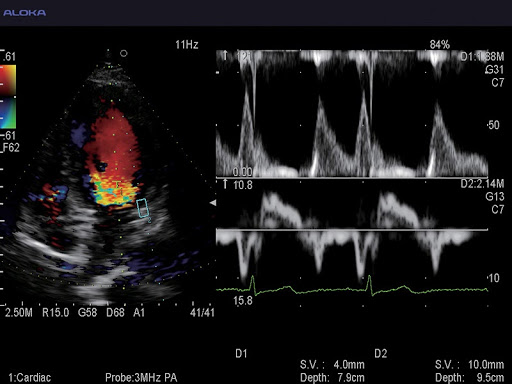

Экспертные функции подойдут для продвинутой диагностики сердечно-сосудистой системы, органов малого таза, вычислений показателей гемодинамики и других узких специализаций. Современные технологии работы с изображениями дают превосходное качество и позволяют извлечь максимум информации. Серошкальная визуализация, допплеровское цветовое картирование кровотока, а также спектральное допплеровское исследование кровотока, которые поддерживает система, позволяют оперативно провести качественные и количественные оценки.

- Стандартные: B, М, D, 2B, 4B, B+M, B+D, B+M+D

- С цветным допплером: 4B, M, B+B, B+M, B+D

- Допплеровские: PW (импульсно-волновой), HPRF (высокочастотный), CW (постоянно-волновой), цветной, энергетический, направленный энергетический, тканевой

Триплексный (B+Color+D)

Экспертная кардиология:

- Фазированные кардиологические датчики для взрослых, детей и новорождённых

UST-52105 – Датчик для проведения эхокардиографических исследований взрослых. Также подходит для транскраниальной допплерографии.